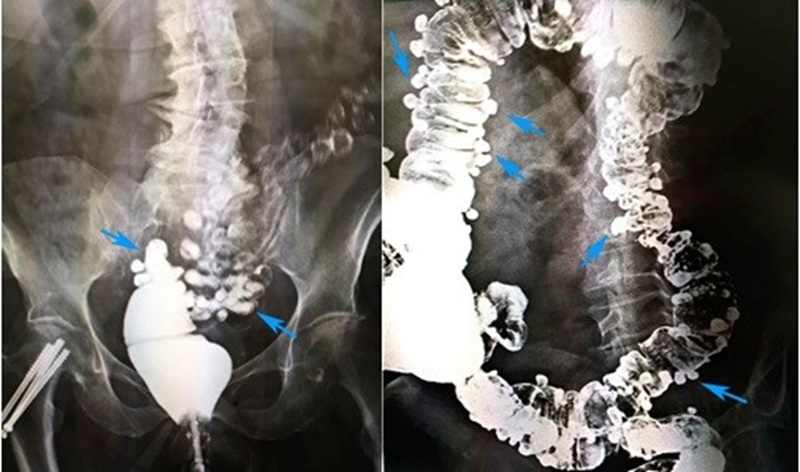

В ходе проктографии используется рентгеновское излучение, контрастные вещества и специальные приборы для создания серии снимков и видеозаписи дефекации. Этот метод позволяет выявить различные аномалии, нарушения или дефекты в работе кишечника, включая ректоцеле, инвагинацию, анизм и энтероцеле. В отличие от стандартной колоноскопии, которая оценивает только состояние слизистой оболочки, проктография дает функциональную оценку всего тазового дна в динамике.

- Применение контрастного вещества. В прямую кишку через тонкий катетер вводится густая бариевая взвесь (или более современное водорастворимое контрастное вещество) комнатной температуры. В некоторых случаях для лучшей визуализации тонкой кишки и влагалища также вводят пероральный и вагинальный контраст.

- Фиксация результатов. Полученные данные фиксируются в виде серии снимков и видеозаписи с высокой частотой кадров, которые будут подробно проанализированы врачом-рентгенологом после завершения процедуры. Врач измеряет ключевые параметры: аноректальный угол, длину анального канала, время эвакуации контраста, наличие ректоцеле и его глубину.